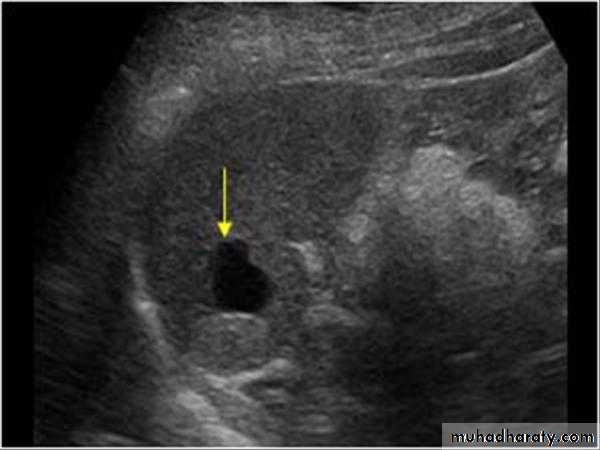

Focal masses ultrasound

Multiple masses